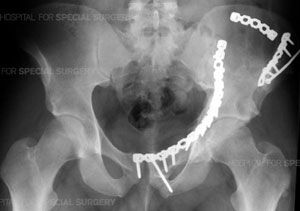

Radiograph of the pelvis following open reduction and internal fixation (ORIF) of a complex comminuted fracture of the left acetabulum, hemipelvis and pubic symphysis.

Patients with acetabular fractures often require an Open Reduction with Internal Fixation (ORIF), especially those patients who also have displacement of the joint. The surgeon realigns or reduces the bones as precisely as possible to prevent the development of post-injury related problems, especially arthritis. The bones are rigidly fixed with plates and screws to prevent future displacement and allow for rehabilitation to begin as quickly as possible.